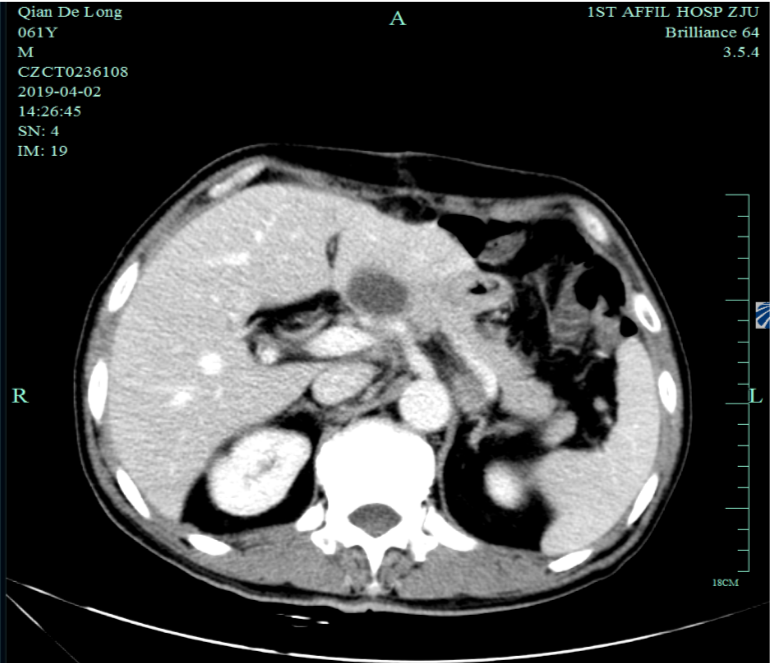

入我院后全面进行评估(2019.4):全腹部CT平扫+增强评估提示腹膜后,胰腺周围多发淋巴结增大,淋巴结转移考虑。

根据AJCC/UICC TNM分期(第8版,2017年):T3N3bM1,IV期

MSH2(+),MSH6(+),MLH1(+),PMS2(+),CK(pan)(+),HER2(EP3)(3+)